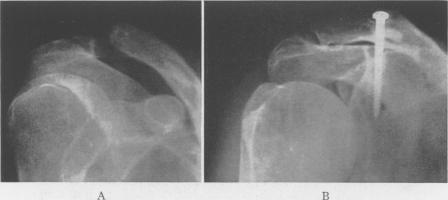

Acromioclavicular Dislocation: End-Results of Screw Suspension Treatment.

Ann Surg. 1948 Jan;127(1):98-111. doi: 10.1097/00000658-194801000-00009.